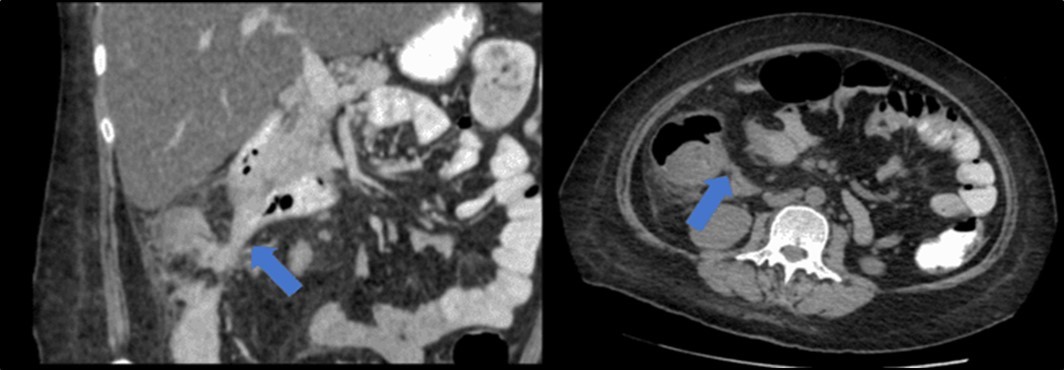

There was no evidence of malignancy or IBD seen during both endoscopic procedures. Computed tomography (CT) scan of the whole abdomen was done which showed inflammatory changes involving the cecum and adjacent duodenum and ileum with coloenteric fistulae. There was noted progression of abdominal lymphadenopathies as well as ascites. Main consideration was an infectious disease process (i.e. TB) (Figure 2, Figure 3, Figure 4 to Figure 5).

Figure 4.Coronal and axial view of the abdomen, the blue arrows pointing towards the suggestive communication to the duodenum